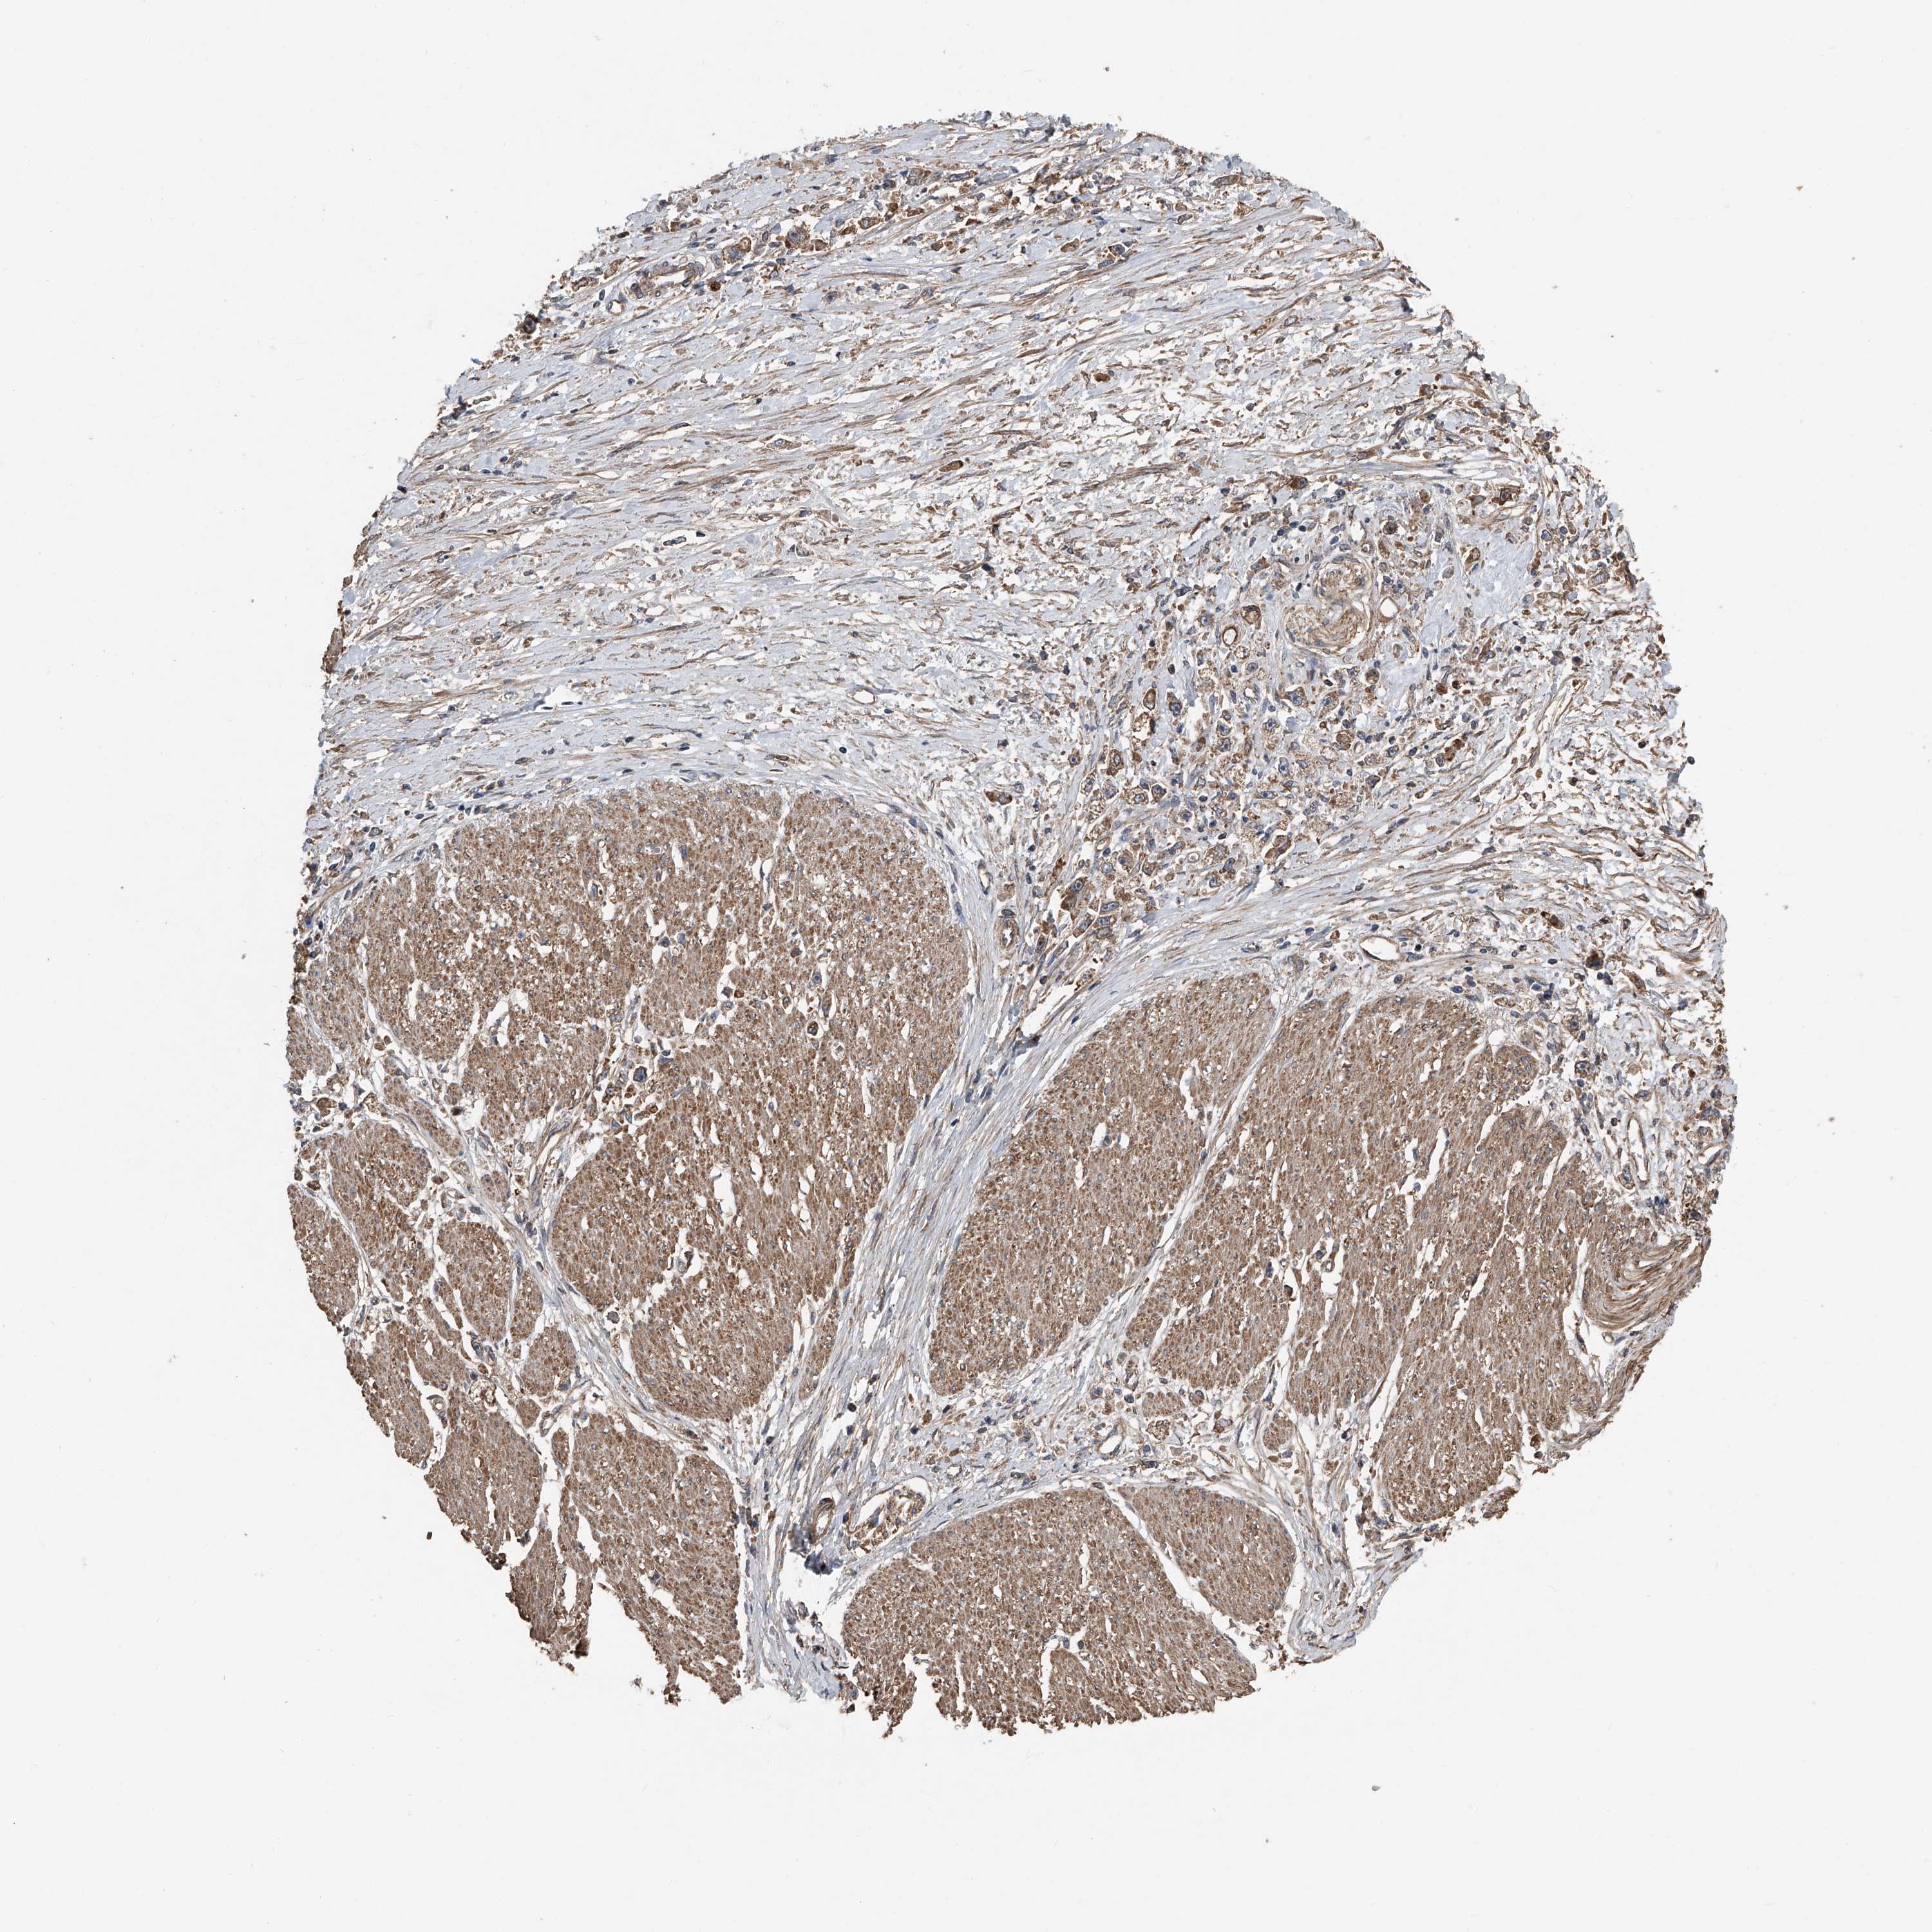

STOMACH CANCER - Protein expressioni

A mouse-over function shows sample information and annotation data. Click on an image to view it in a full screen mode. Samples can be filtered based on level of antibody staining by selecting one or several of the following categories: high, medium, low and not detected. The assay and annotation is described here.

Note that samples used for immunohistochemistry by the Human Protein Atlas do not correspond to samples in the TCGA dataset.

Antibody stainingi

Antibody staining in the annotated cell types in the current human tissue is reported as not detected, low, medium, or high, based on conventional immunohistochemistry profiling in selected tissues. This score is based on the combination of the staining intensity and fraction of stained cells.

Each image is clickable and will lead to virtual microscopy that enables deeper exploration of all samples and also displays staining intensity scores, fraction scores and subcellular localization as well as patient and tissue information for each sample.

Antibody HPA029109

Staining

High

Medium

Low

Not detected

Intensity

Strong

Moderate

Weak

Negative

Quantity

>75%

75%-25%

<25%

None

Location

Nuclear

Cytoplasmic/membranous

Cytoplasmic/membranous,nuclear

Adenocarcinoma, NOS